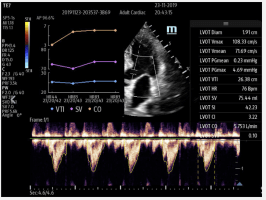

Smart Velocity Time Integral (Smart VTI) – Automated Velocity Time Integral (VTI) and Cardiac Output (CO) measurements enable rapid cardiac function assessment. This software automatically locates the color box and Pulse Wave (PW) Doppler sample line in real-time. A graph of parameter trends for CO, Stroke Volume (SV), and VTI is produced to guide decision-making.

Smart Velocity Time Integral (Smart VTI) – Automated Velocity Time Integral (VTI) and Cardiac Output (CO) measurements enable rapid cardiac function assessment. This software automatically locates the color box and Pulse Wave (PW) Doppler sample line in real-time. A graph of parameter trends for CO, Stroke Volume (SV), and VTI is produced to guide decision-making.